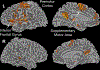

Results: During light sedation, the spatial extent of auditory/motor activation was similar, becoming restricted to the superior temporal gyrus during deep sedation. Region of interest analysis revealed significant activation in the superior temporal gyrus during light (t [17] = 9.71, P < 0.001) and deep sedation (t [19] = 3.73, P = 0.001). Spatial extent of the phonologic contrast decreased progressively with sedation, with significant activation in the inferior frontal gyrus maintained during light sedation (t [35] = 5.17, P < 0.001), which didn't meet criteria for significance in deep sedation (t [38] = 2.57, P = 0.014). The semantic contrast showed a similar pattern, with activation in the angular gyrus during light sedation (t [16] = 4.76, P = 0.002), which disappeared in deep sedation (t [18] = 0.35, P = 0.731).

Conclusions: Results illustrate broad impairment in cognitive cortex during sedation, with activation in primary sensory cortex beyond loss of consciousness. These results agree with clinical experience: a dose-dependent reduction of higher cognitive functions during light sedation, despite partial preservation of sensory processes through deep sedation.